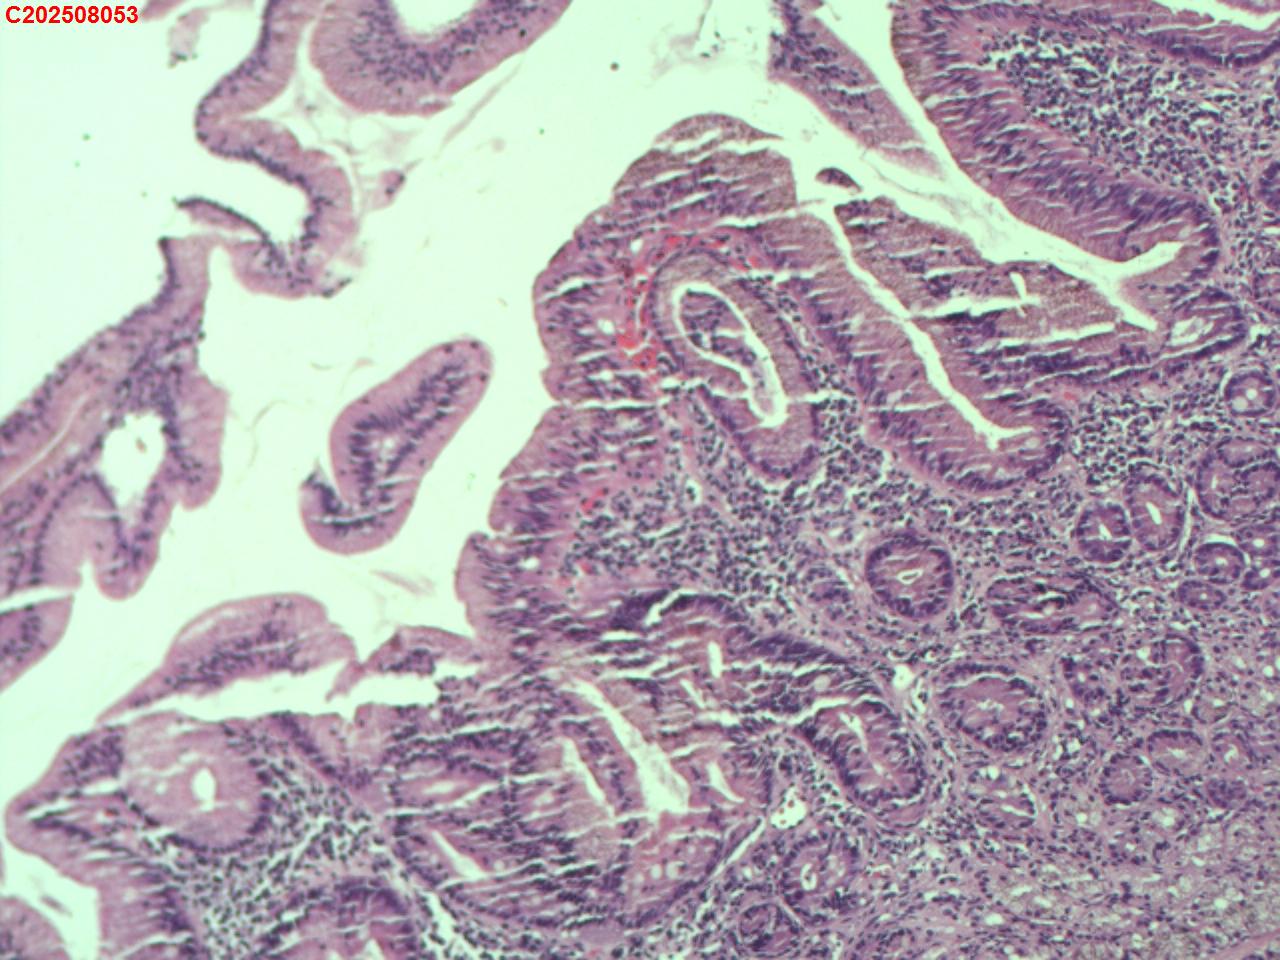

十二指肠黏膜

十二指肠球部息肉

十二指肠球部黏膜

十二指肠球部可见一息肉样隆起。

图2

增生性息肉。